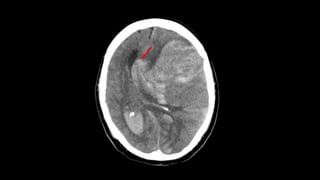

2) Lesões focais com efeito de massa

❑ Início: processo localizado / assimetrias ao exame

❑ Com aumento de PIC 🡪 Herniação

❑ Quadro com piora progressiva

❑ Obs: respostas motoras assimétricas e movimentos oculares anormais persistem

até estágios terminais

❑ Grau de alteração de consciência é relacionado a grosso modo com volume de

tecido cerebral afetado

CAUSA: I - Estrutural Supratentorial

• Trauma:

– lesão axonal difusa

– Sangramentos intracranianos:

. Hematomas subdurais ou extradurais

. HIP

. HSA traumática

• Vascular:

– AVCs 🡪 hemorragias/ isquemia cerebral extensa / vasoespasmo

por HSA aneurismática

– Isquemia talâmica bilateral

– Trombose de seio cerebral